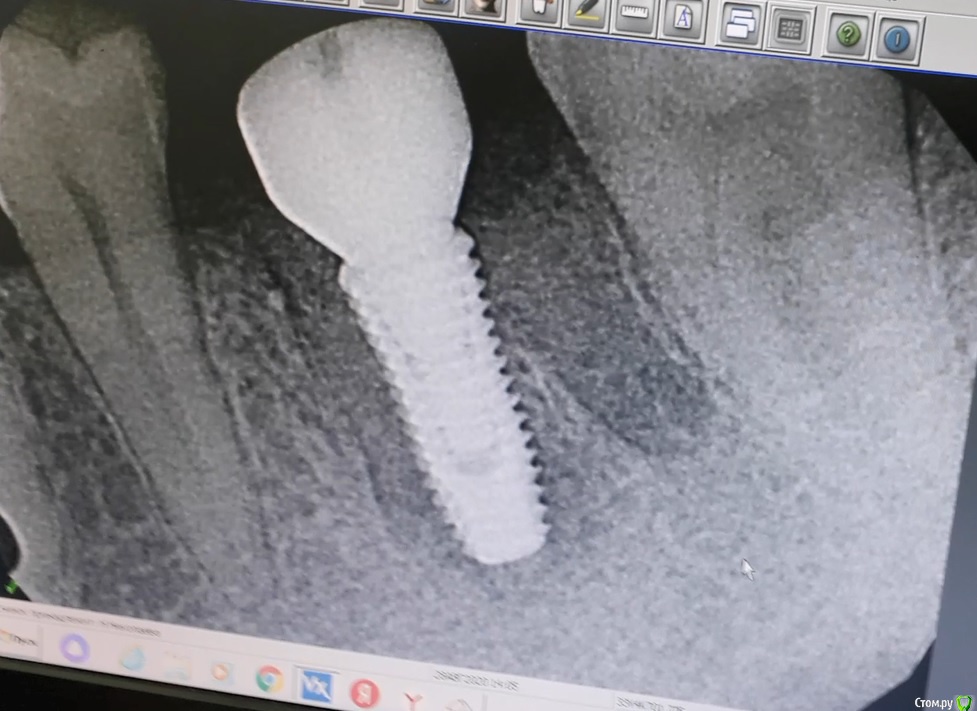

Nata26 Опубликовано 28 августа, 2020 Автор Поделиться Опубликовано 28 августа, 2020 Сделала прицельный снимок имплантата сегодня. Вообще, при одномоментной имплантации с установкой формирователя десны в норме сколько могут длиться боли? Ссылка на комментарий

Irouil Опубликовано 28 августа, 2020 Поделиться Опубликовано 28 августа, 2020 Снимок выглядит нормально, выраженные болевые ощущения обычно держатся не более недели Ссылка на комментарий